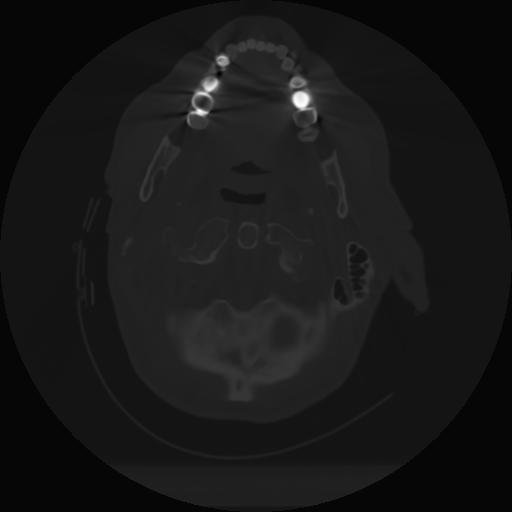

10 P.BLANDAS,,Axial,2.0,P.BLANDAS,,